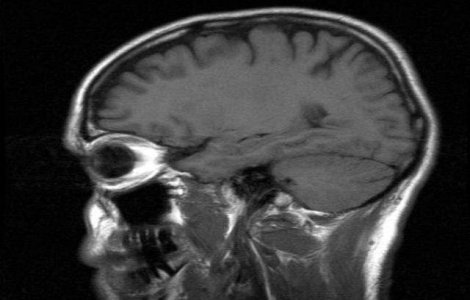

Creierul are o regiune care este responsabila de instalarea schizofreniei si a maladiei Alzheimer,

Anumite specii de animale sunt considerate cele mai inteligente din lume, deoarece animalele poseda creiere ce au caracteristici asemanatoare celor umane